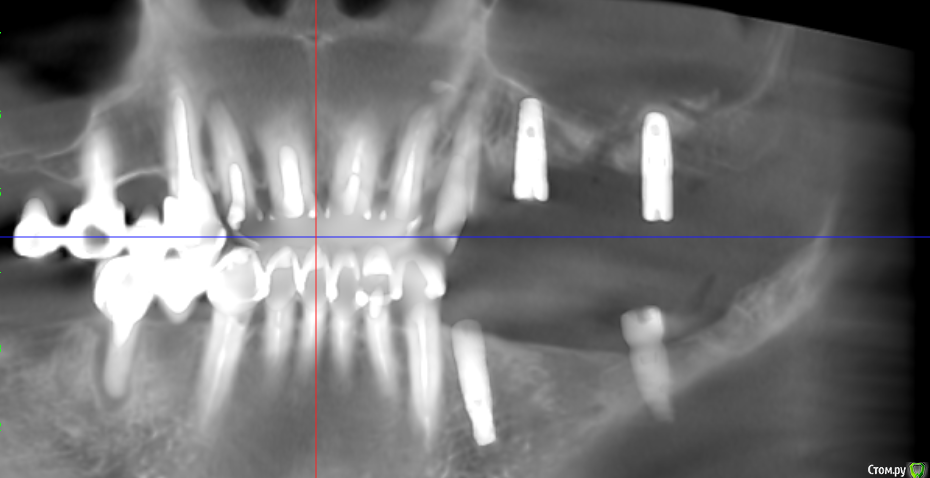

V20 Опубликовано 28 апреля, 2019 Поделиться Опубликовано 28 апреля, 2019 (изменено) Доброго времени суток , помогите пожалуйста разобраться с ситуацией.В мае 2018 года был проведен синус лифтинг с одновременной установкой 3 имплантов, Спустя 5-7 дней на фоне приема антибиотиков(Аугментин), развился левосторонний гайморит. Прошел курс консервативного лечения, пазуха успокоилась.Было решено протезироваться . В феврале 2019 года при откручивании ФД выкрутился имплант (по центру ) и образовался свищ, . Была сделана пластика свища. Сообщение закрылось.На настоящий момент сохраняется чуть заметная припухлость щеки в проекции пазухи и немного поднывает десна.(больше в районе крайнего импланта) На ощупь языком в месте соприкосновения десны и щеки небольшая припухлость ( похоже по проекции разреза).Что интересно с утра десна не болит начинается дискомфорт чуть позже. Уважаемые доктора , помогите пожалуйста в дальнейшей тактике - мнения врачей кардинально расходятся(снимки через неделю после синус лифтинга Снимок 3 месяца назад после консервативного лечения у ЛОРа Последний снимок (2 месяца назад) И еще хотелось бы услышать Ваше мнение о импланте на месте 24 зуба Заранее спасибо. Изменено 28 апреля, 2019 пользователем V20 Ссылка на комментарий